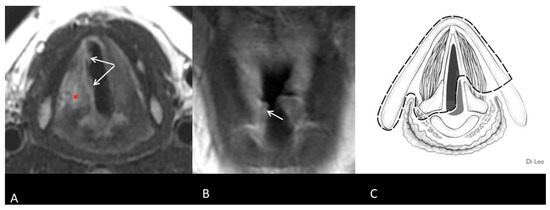

- Maroldi, R.; Ravanelli, M.; Farina, D. Magnetic resonance for laryngeal cancer. Curr. Opin. Otolaryngol. Head Neck Surg. 2014, 22, 131–139. [Google Scholar] [CrossRef]

- Ferreiro-Argüelles, C.; Jiménez-Juan, L.; Martínez-Salazar, J.M.; Cervera-Rodilla, J.L.; Martínez-Pérez, M.M.; Cubero-Carralero, J.; González-Cabestreros, S.; López-Pino, M.A.; Fernández-Gallardo, J.M. CT findings after laryngectomy. Radiographics 2008, 28, 869–882; quiz 914. [Google Scholar] [CrossRef]